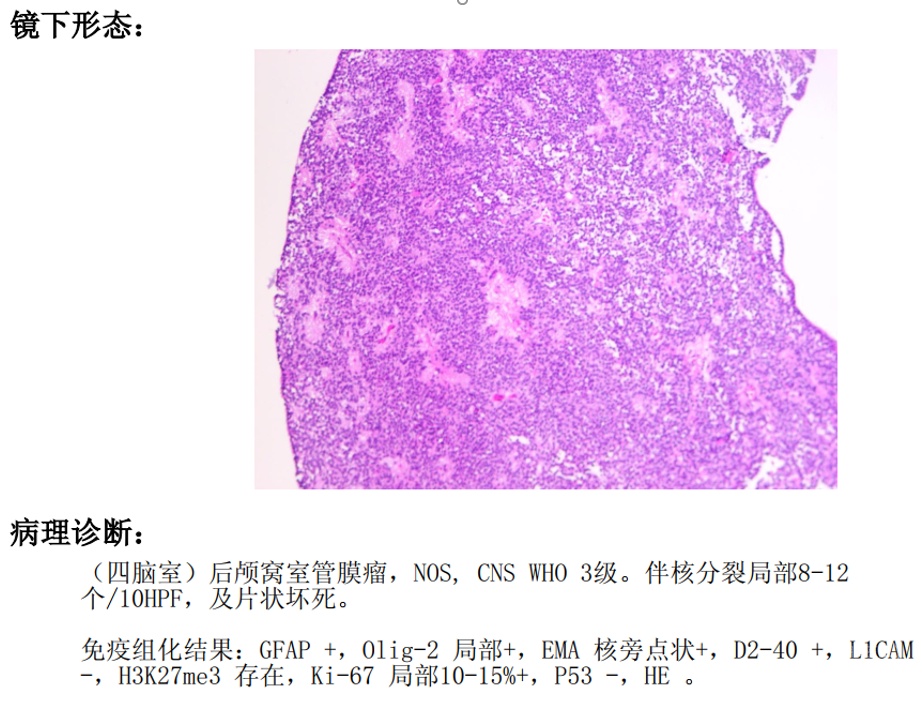

术后病理及后续治疗

术后病理提示室管膜瘤,WHO III级。术后拟行放疗治疗。